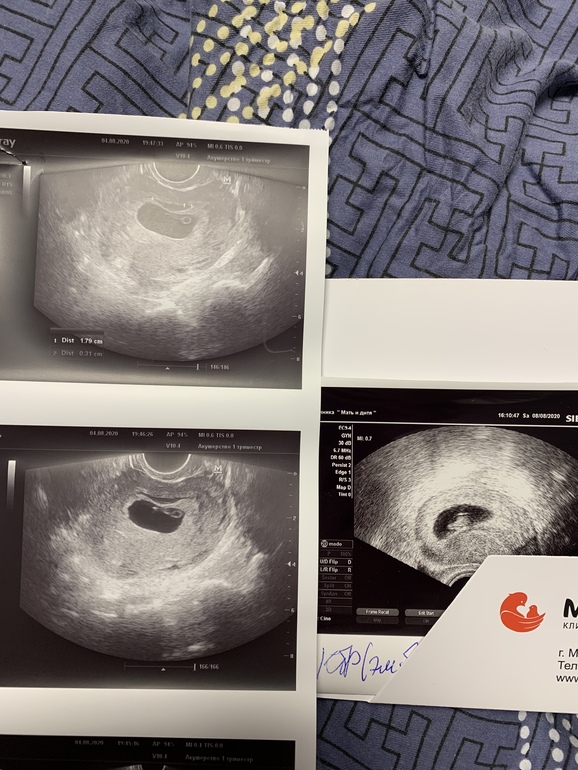

Яна,вот твой пример не даёт мне унывать.Надеюсь у меня тоже сейчас пойдёт в рост.Если так посчитать,то у меня тоже растёт на 3 мм в неделю. Вот узи с разных аппаратов.Все будет хорошо 🙏главное рост есть.А то я что-то приуныла.Ре меня отпустила уже,но наверное схожу ещё раз недели через 2-3 к ней.На учёт уже можно.Но мне кажется ЖК ещё не возьмёт.Они страховщики те ещё.

Да,вы правы. Я даже сравнила снимки